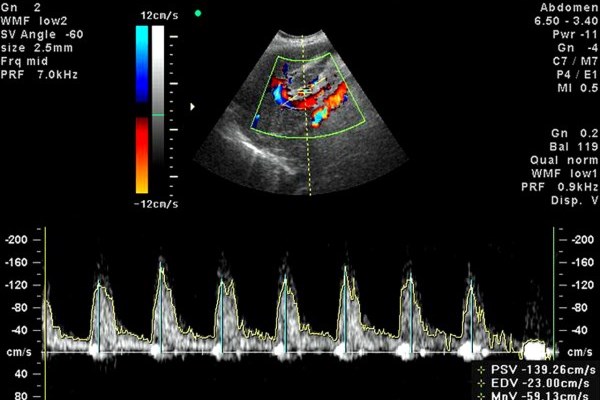

Доплер-режим используется для оценки скорости и типа кровотока через клапаны. Его принцип – это отражение ультразвука от движущихся частиц. В кровотоке такими частицами являются эритроциты. Сигнал отражается от них по-разному, в зависимости от того, движутся ли эритроциты в крови от датчика или по направлении к нему.

Есть 3 режима доплеровского исследования. Первый вариант – это постоянно-волновой режим, при котором врач оценивает все потоки по указанной линии. По полученному графику и форме дают оценку правильность всех фаз движения крови через клапан и максимальную скорость на всей глубине. Недостаток режима: нельзя точно узнать, где именно точка максимальной скорости.

Второй вариант – импульсно-волновой режим, который нужен, чтобы узнать максимальную скорость в конкретной точке. В этом режиме датчик посылает сигнал в виде нескольких импульсов, а потом ждет его возвращения от эритроцитов.

Оба режима нужны для количественной и качественной оценки параметров гемодинамики. Данные врач фиксирует и указывает в заключении.

Третий вариант исследования – это цветовое доплеровское картирование. Если врач включает цветной доплер, то кровоток окрашивается в сине-красные цвета. С помощью цвета можно выявить обратное движение крови при клапанной недостаточности (регургитацию), аномальное ее движение через перегородки при врожденных пороках, турбулентный ток крови при сужении отверстия клапана.